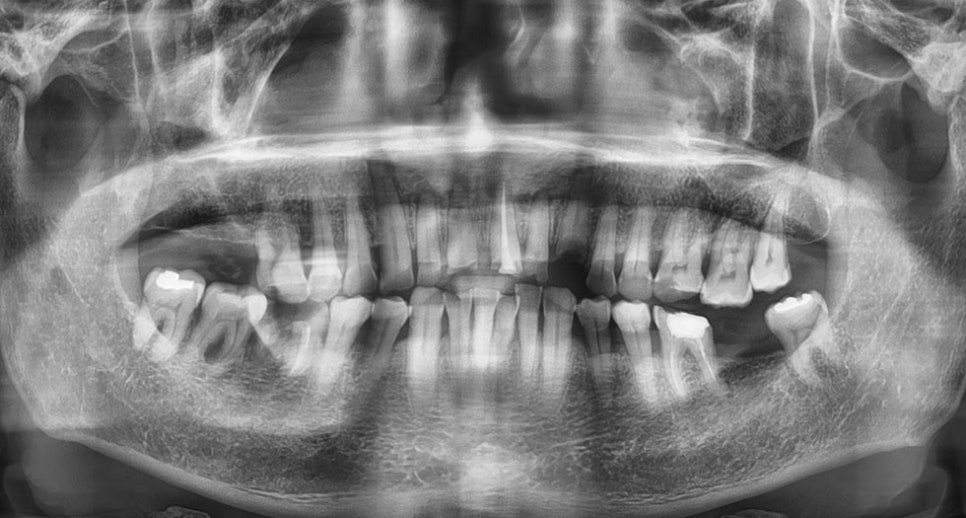

위 사진은 뉴엔임플란트센터에서의

CT 모의술식의 한 장면이며 미리 뼈와

기타 구조물들을 분석하여 임플란트 수술 전

다양한 상황을 예측하고 시뮬레이션 후

시행하고 있습니다.